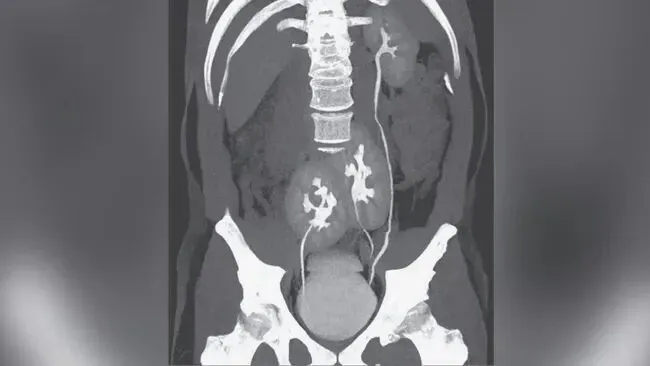

Qua siêu âm bụng và chụp CT, các bác sĩ phát hiện bệnh nhân có quả thận thứ ba, còn được gọi là "thận thừa". Quả thận thừa này nằm ở bên phải và được nối với quả thận phải ban đầu, tạo thành cấu trúc tổng thể hình móng ngựa.

Tính độc đáo của trường hợp này nằm chủ yếu ở hai khía cạnh. Thứ nhất, bản thân "quả thận thừa" cực kỳ hiếm gặp, với chưa đến 100 trường hợp mới được báo cáo trên toàn cầu mỗi năm; thứ hai, quả thận thừa đã hợp nhất với quả thận hiện có để tạo thành cấu trúc hình móng ngựa.Những trường hợp như vậy thậm chí còn hiếm gặp hơn , chỉ có rất ít báo cáo trong các tài liệu khoa học hiện có.

Cần lưu ý rằng thận phụ có sự đa dạng đáng kể về mặt giải phẫu. Ở một số người, thận thứ ba có thể tồn tại hoàn toàn độc lập , hoặc chỉ được kết nối với thận bên cạnh bằng một lớp mô mỏng. Chức năng của nó cũng có thể bình thường hoặc khác biệt. Những phát hiện tình cờ như vậy không phải là hiếm. Ví dụ, Tạp chí Y học New England (NEJM) đã đưa tin vào năm 2020 rằng một người đàn ông Brazil đi khám bệnh vì đau lưng do thoát vị đĩa đệm đã bất ngờ phát hiện ra thận thứ ba trong khi chụp CT. Thận phụ này nằm gần vùng chậu và được kết nối với thận phải, nhưng cả ba thận đều hoạt động bình thường và không được coi là nguyên nhân trực tiếp gây ra các triệu chứng của ông.